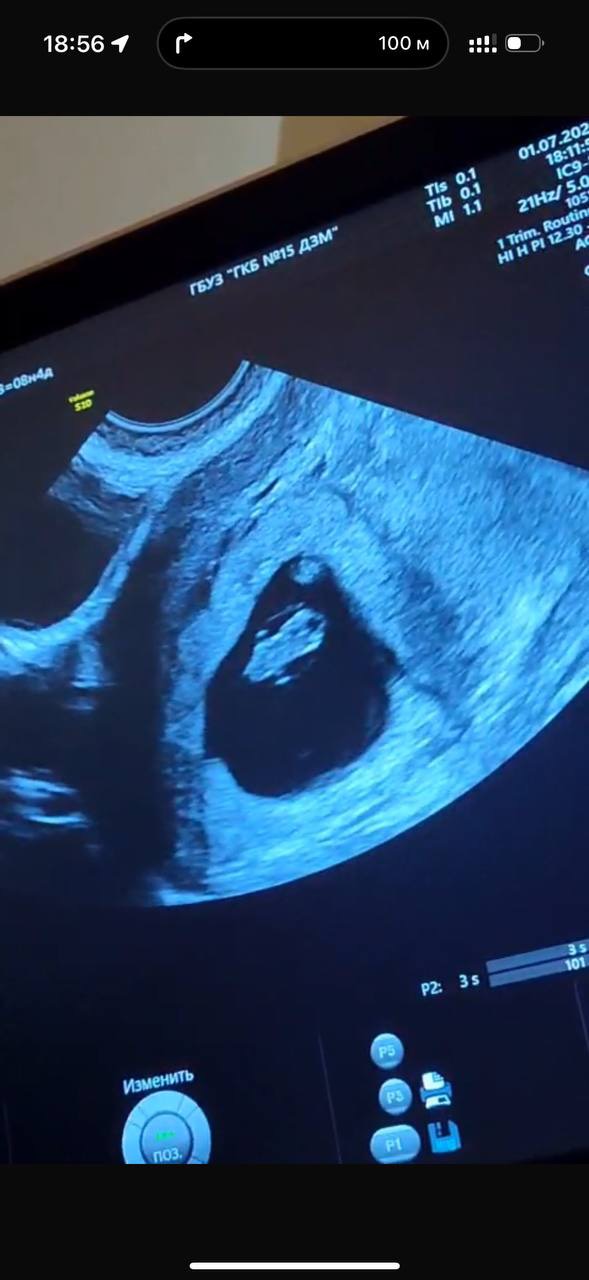

А вот и фото с УЗИ 😍 я даже поверить не могу, что это уже целый организм с бьющимся сердечком, проявляющимися ручками и головой 🥹

Огромное спасибо 😊 когда мне показывали ручки, и показали как бьется сердце , я не верила, что это во мне 🤰🏼 поначалу даже какой-то легкий страх был, но потом муж успокоил сказал «не дури, пойдем поедим нормально»))) а то мы же спортсмены с ним 😃 большое спасибо! Не буду! Даже кондиционеры не включаю лишний раз! И только 23-25 градусов !)